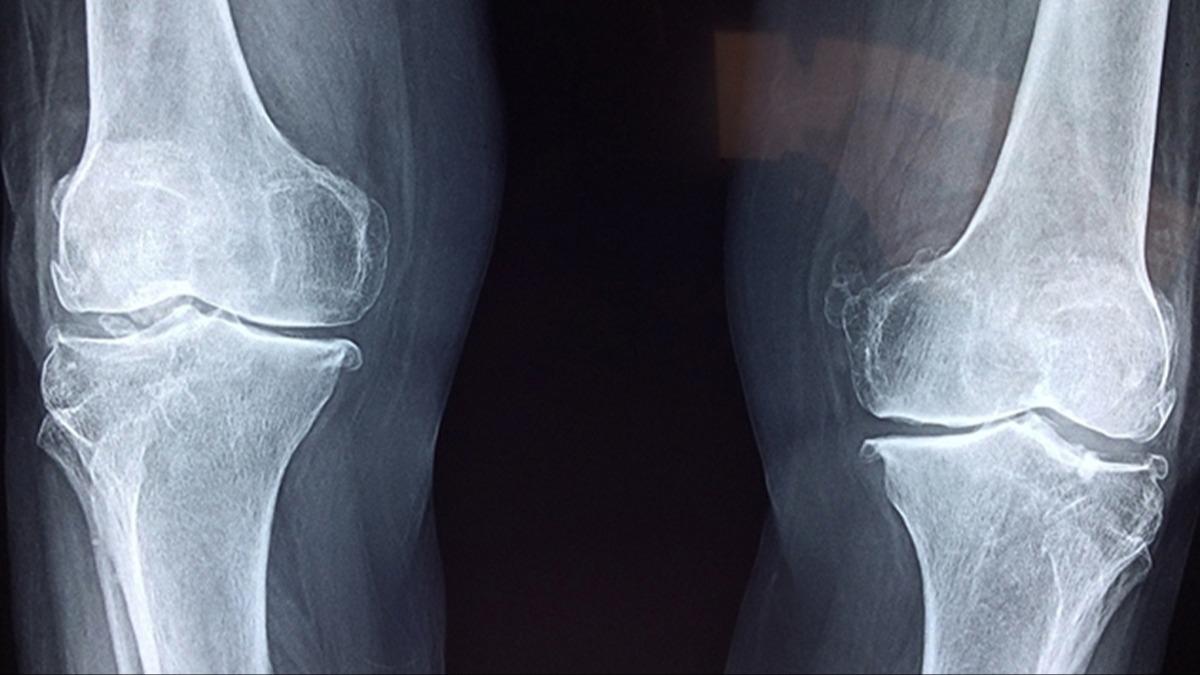

Sert dizler, ağrıyan kalçalar ve kronik eklem ağrısının yavaş yavaş ilerlemesi genellikle yaşlanmanın kaçınılmaz bir parçası olarak kabul edilir. Ancak osteoartrit dünyanın en yaygın eklem hastalığı olmasına rağmen, uzmanlar bu hastalığı tedavi etme ve önleme konusundaki yaklaşımımızın bilimsel kanıtlarla ciddi şekilde uyumsuz olduğunu vurguluyor.

Bu rakamların neden bu kadar rahatsız edici olduğunu anlamak için, egzersizin eklemler için ne yaptığını bilmek gerekir. Osteoartrit açık ara en yaygın artrit şeklidir ve halihazırda dünya çapında 595 milyondan fazla insanı etkilemektedir. The Lancet'teki küresel bir çalışmaya göre, bu sayı 2050 yılına kadar bir milyara yaklaşabilir. Daha uzun yaşam beklentisi, giderek hareketsiz yaşam tarzları ve artan sayıda fazla kilolu veya obez insan bu endişe verici eğilimi yönlendirmektedir.

Artık osteoartritin sadece kıkırdağı etkileyen bir sorun değil, tüm eklemi etkileyen kapsamlı bir hastalık olduğunu biliyoruz. Eklem sıvısını, alttaki kemiği, bağları, çevredeki kasları ve hatta hareketi destekleyen sinirleri etkiler. Terapötik egzersiz tüm bu unsurları hedeflemektedir.